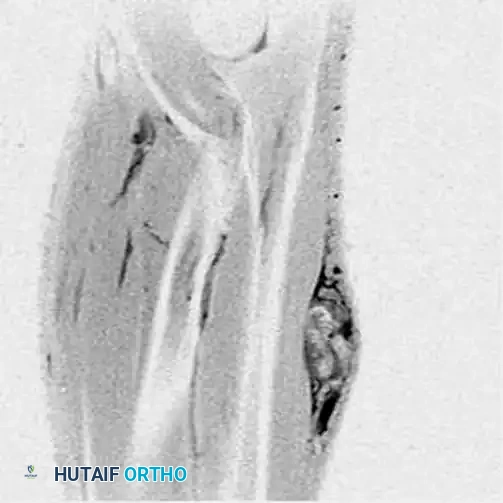

Imaging and Pathology:

Plain radiographs show amorphous, stippled calcifications within the soft-tissue mass in up to 30% of cases. Genetically, they are characterized by the pathognomonic t(X;18) chromosomal translocation.

AP radiograph of the wrist in a 67-year-old patient showing irregular calcifications within a soft-tissue mass.

CT scan better delineating the intralesional calcifications.

MRI demonstrating the full extent of the synovial sarcoma in the distal forearm/wrist.